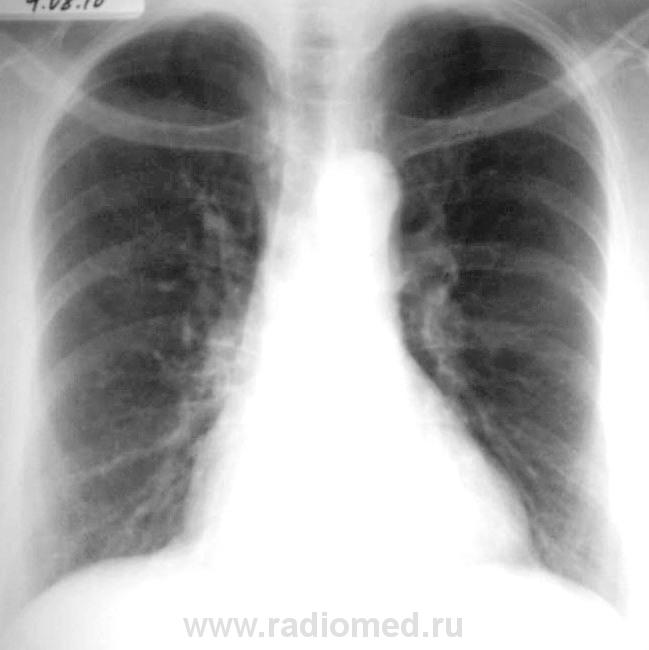

Р-графия грудной клетки. Женщина 58 лет.

Женщина 58 лет. Беспокоит кашель, иногда с мокротой. Из анамнеза болеет лёгкими с детства, частые бронхиты, пневмонии. 2 раза в год лечится в стационаре по поводу хр. бронхита.

Вроде ничего не пропускаем. Признаки ХОБЛ, клинически - обострение...

А я бы сделала правый бок, что за округлая тень прилежащаяя к средней части корня справа? Слева в корне прослеживаются сосуды.

Да поторпился справа есть тенюха...

Свежего процесса не видно. Локальный перибронхиальный фиброз (промежут. бронха) справа...

"Свежего процесса не видно." Видны бронхоэктазы цилиндрические средней доли, которые, вероятно, и провоцируют частые обострения лёгочной патологии, расцениваемые клиницистами как обострение хр. бронхита.